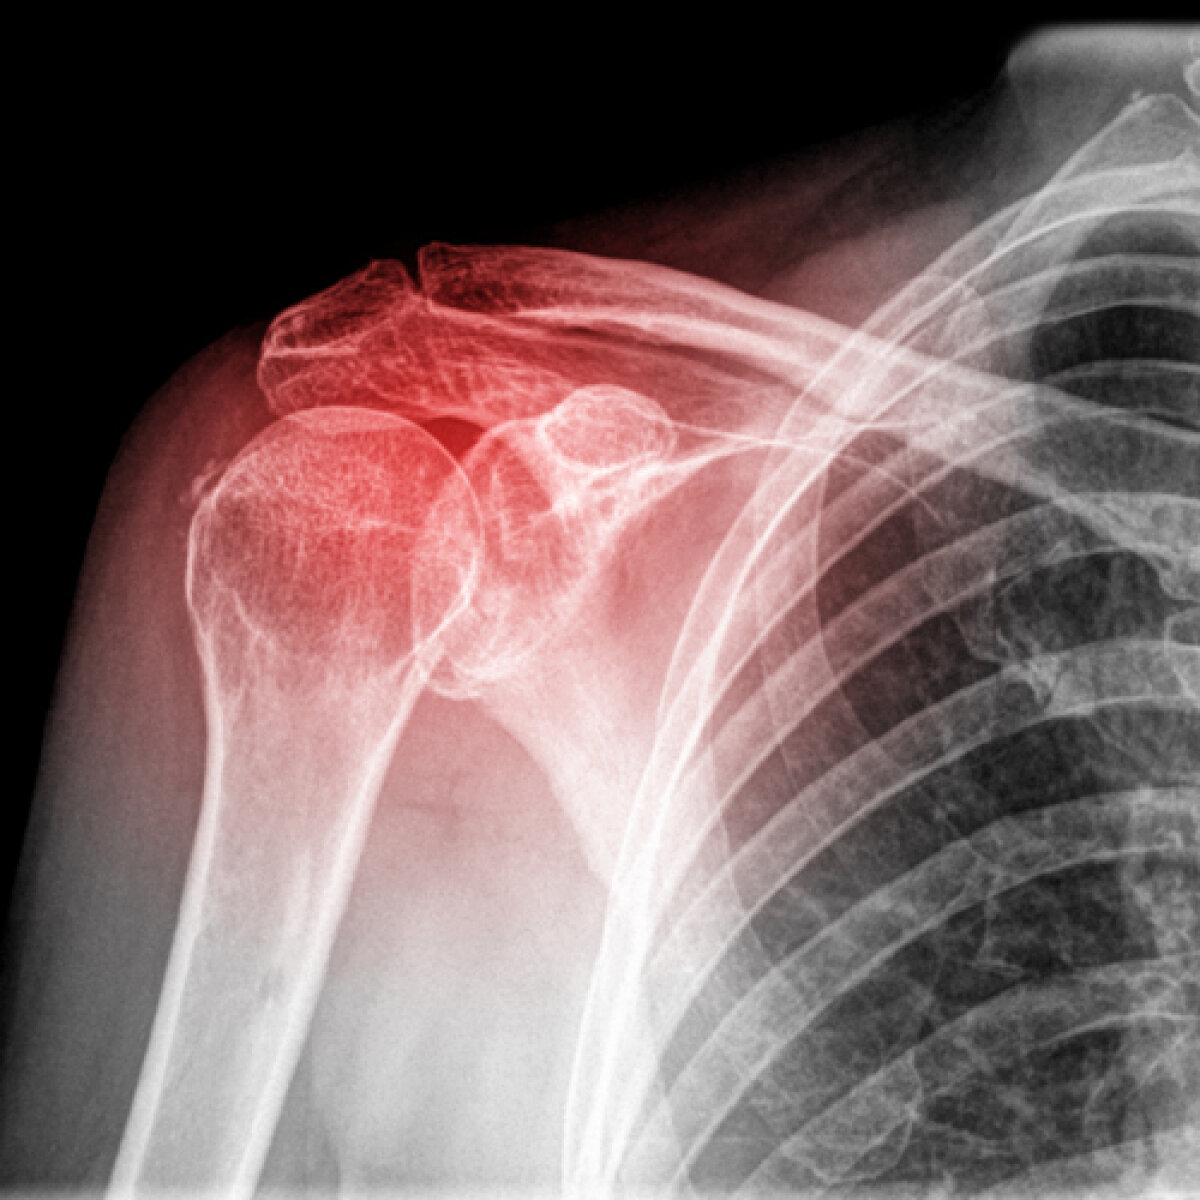

Foto 5/5 : Cariera Cristinei Neagu depinde de operaţia la umărul drept.